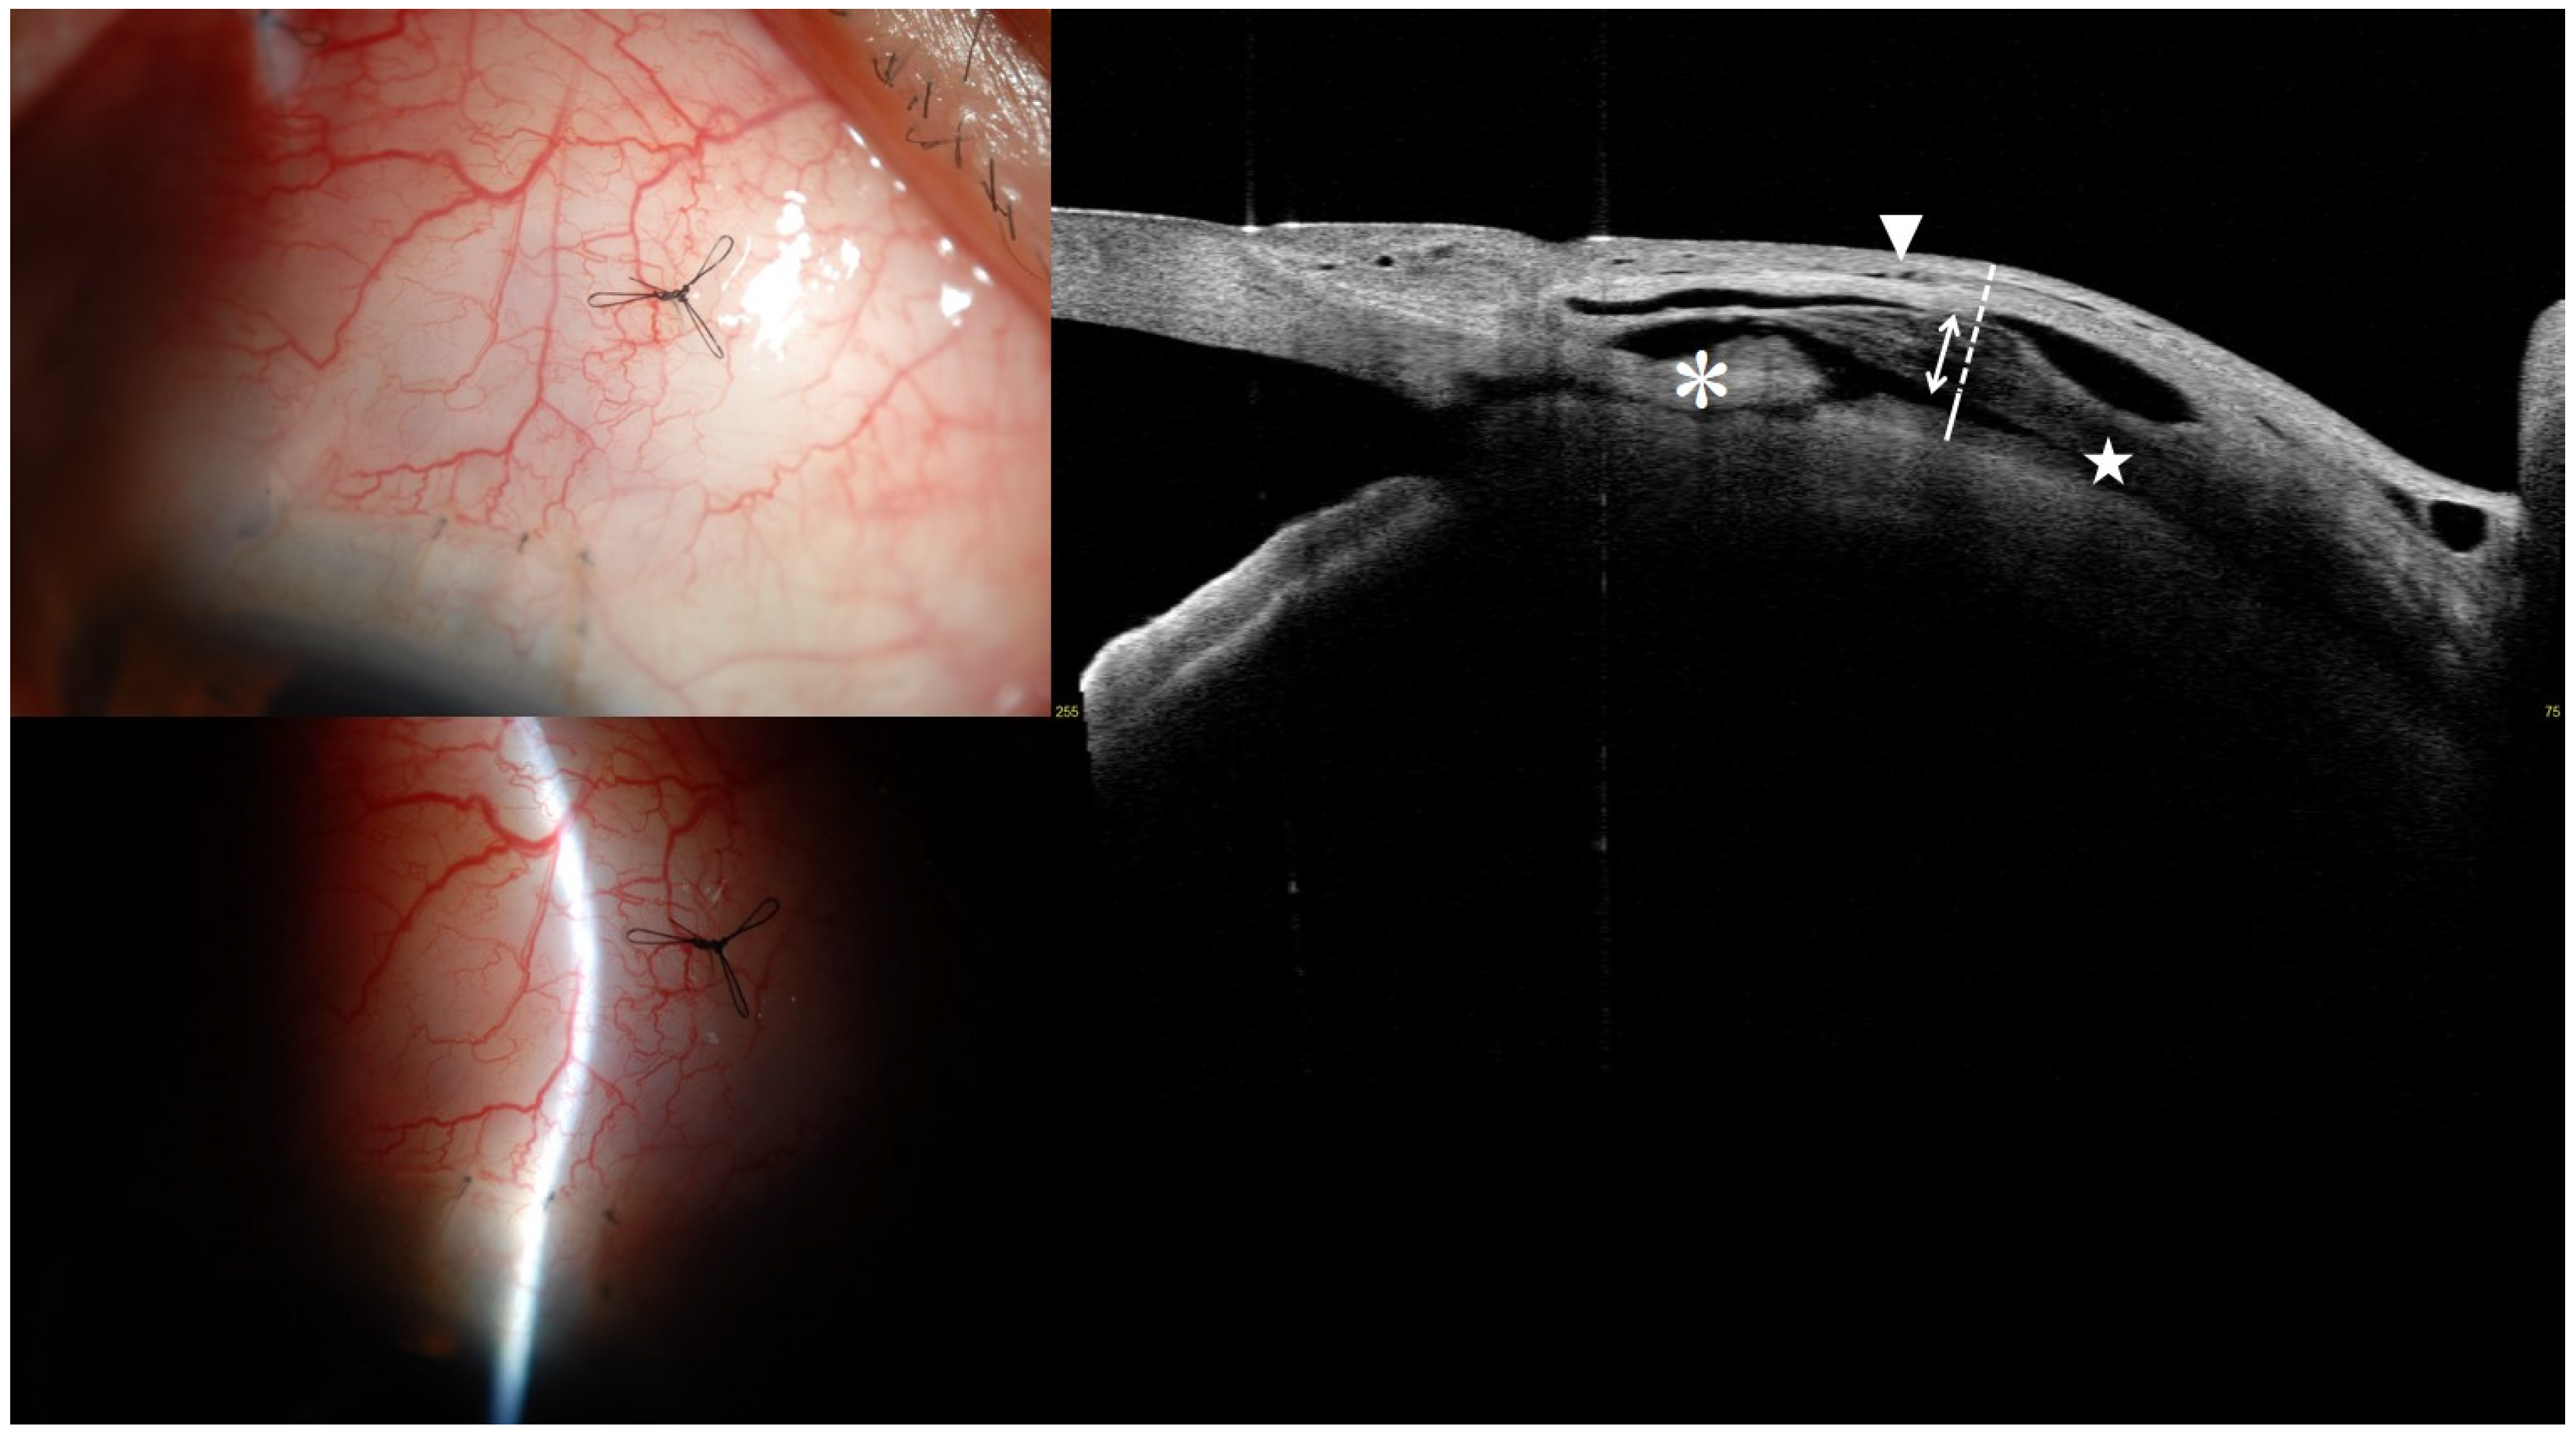

3.4. Representative Anterior Segment Optical Coherence Tomography Images at 1 Month